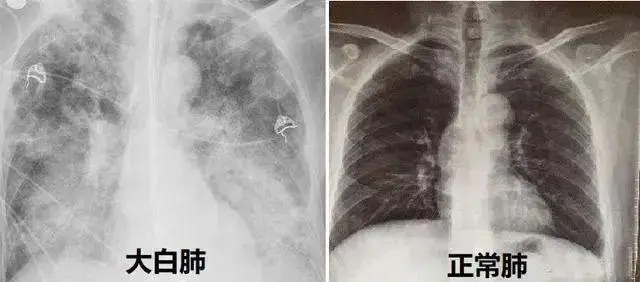

首先要明确一点,"白肺"只是医学临床工作上的一种口语化的表达方式。通常患者肺部出现炎症,并且随着炎症逐渐加重,肺部也会出现越来越多发白的情况。通常情况下,在CT影像中,如果白色区域超过75%,通常就会称其为"白肺"。

"白肺"指代的是比较严重的肺部感染问题,但并不是只有新冠病毒会导致"白肺"。普通的肺炎,肺部感染问题,只要感染较为严重同样有可能导致"白肺","白肺"并不是新冠病毒感染的标志,这一点我们需要注意区分。